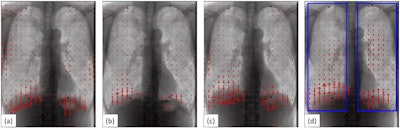

A 65-year-old male COPD patient with 38.5 FEV1% and percent predicted %FEV1 16.3, which meets the criteria of severe COPD. Blue rectangles (d) represent bilateral regions of interest. VF-DXR images in (a) tidal inspiratory, (b) tidal expiratory, (c) forced inspiratory, and (d) forced expiratory phase. (e) The graph shows the temporal change between LMV in the right lung and the number of frames. The frame rate is set to 5 frames/s (Video 2 in the Supplemental material). Images courtesy of European Radiology Experimental.Lung motion velocity among groups characterized as being normal, having mild COPD, or having severe COPD were different in the tidal respiration, the researchers stated. The COPD mild group showed a significantly larger magnitude of lung motion volume compared with the normal group, they added.